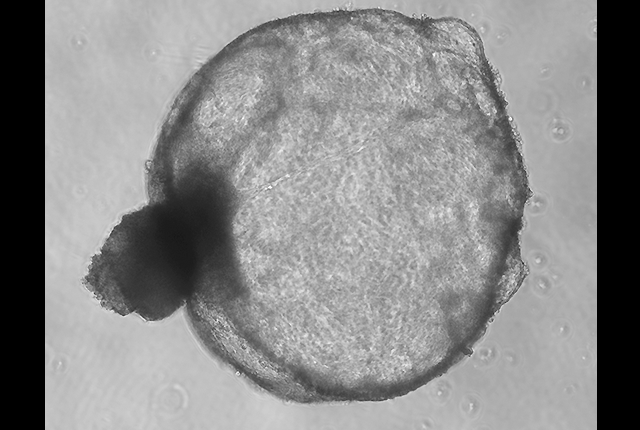

“It's a novel idea to have tiny organoids that respond in the same exact way that a kidney would. You see (polycystic kidney) disease materialize before your eyes. The cyst structures that are characteristic of the disorder, you can see in three dimensions,” he said.

Polycystic kidney disease, commonly called PKD, affects 12.5 million people worldwide and is one of the most common inherited genetic disorders. The disease is characterized by fluid-filled sacs that develop in the kidneys and curb the organs' function. Patients typically show symptoms in their 30s, progress rapidly and need kidney transplants by their 50s. Aside from the faltering kidneys, other organ systems decline in parallel.